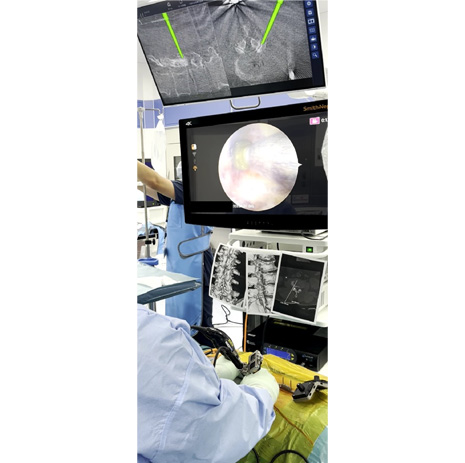

手術ナビゲーションシステムとは

せぼねの手術で用いられるナビゲーションシステムは、手術を安全に行うための機器になります。せぼねの病気はさまざまあり、患者さんによって病気の部位や骨の変形は異なります。また、せぼねの周りには大事な神経組織や血管が位置しているため、これらを傷つけないように手術が行われる必要があります。これまでは透視装置などを駆使して手術が行われていました。しかし、固定術で施行されるスクリューの誤設置や固定材料の不適切な設置がなされる場合がありました。

当院では様々な種類のナビゲーションシステムを採用しています。そのため、手術はより安全に行われ、手術時間の短縮、出血量の低減、被爆量の減少、さらには早期復帰につながるものと考えています。

ナビゲーションシステムを用いた

内視鏡手術

ナビゲーションシステムを用いた内視鏡手術